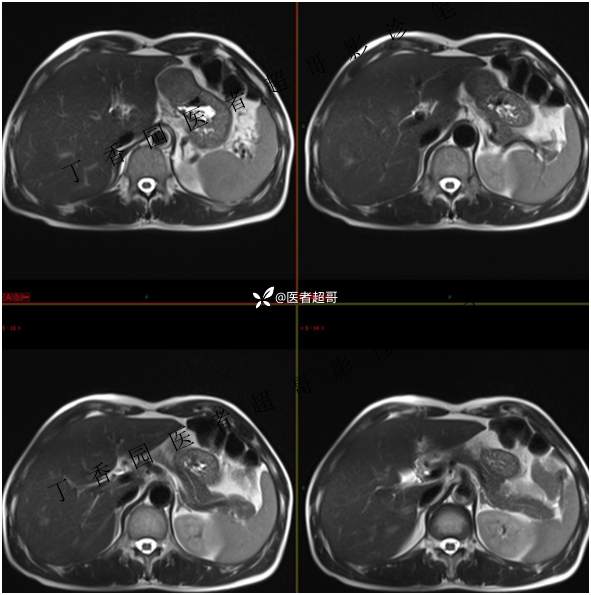

肝胃间隙肿瘤,间质瘤?平滑肌瘤?还是鞘瘤?有结果,请分析!

现病史:患者于3天前查体行肝胆脾胰肾彩超示肝内实性占位,无恶心、呕吐,无发热、寒战,无腹胀、腹泻,进一步于医院行上腹部CT增强示:肝胃交界处肿块。未行特殊治疗。今患者为求进一步治疗,来我院就诊,门诊以“肝占位性病变”收入院。患者自发病以来,神志清,精神可,饮食睡眠可,二便可,体重近期未见明显变化。